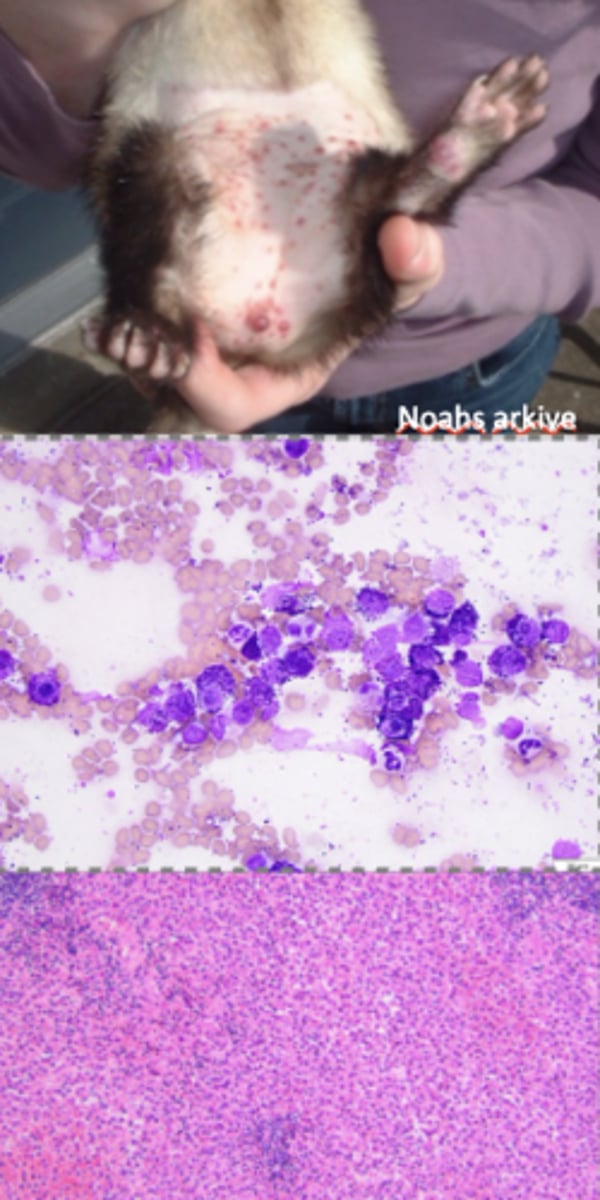

Mast cell tumor

What kind of round cell tumor is this?